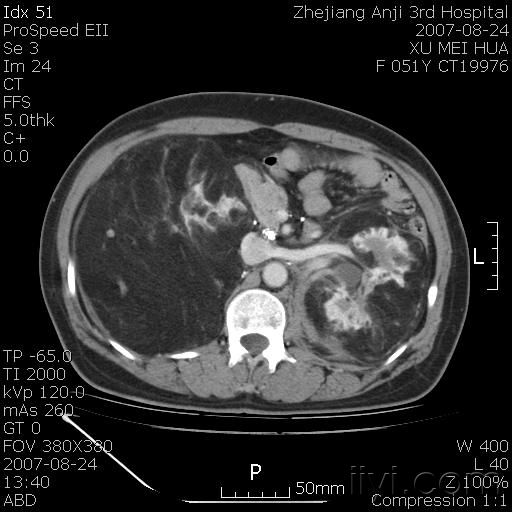

以下是引用还珠格格在2007-8-27 10:19:00的发言:[br]双侧肾脏形态失常,可见巨大的以低密度脂肪为主的混合性肿块,占据中下腹,残留的肾组织轻度强化,增强后肿块内实质部分呈峰窝状强化,低密度区无强化。另左侧肾盂轻度积水。根据病史 考虑 双肾血管平滑肌脂肪瘤可能性大。[br] 鉴别诊断 1、脂肪瘤,境界清楚,肿块内完全是脂肪,几乎没有软组织成分; 2、畸胎瘤:罕见,除有软组织成分外,另一特征是有钙化或骨化影组织。